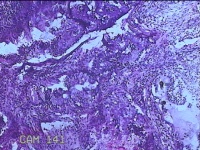

宫颈组织

性别

女

年龄

44岁

临床诊断

宫颈赘生物

一般病史

发现宫颈赘生物2年余。

标本名称

大体所见

灰白暗红色组织3.8x1.5x0.8cm一块,表面光滑,以宫颈12点缝线标记处切开,切面灰白粉红色,质软,宫颈3点处见灰白粉红色囊性肿物1.8x1.5x0.3cm一个,切开肿物,内见大量乳白色内容物,囊壁厚0.1cm。